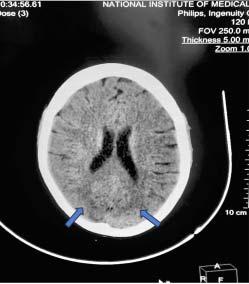

Hospital records such as admission certificate, treatment records, bed head tickets were reviewed for the purpose of selection of cases and controls (Fig 1).

During the reference period those attending the post COVID-19 follow-up clinic were included into the study

Those who provided written, informed consent, and satisfied the inclusion and exclusion criteria were included in the study. (n=64)

Medical records of the subjects were reviewed and participants were consecutively enrolled and categorised as cases and controls*

Three controls were taken against each case, matched appropriately with respect to age (±2 years) and sex.

Those who had severe COVID-19 disease (as per WHO guidelines) were taken as cases (n= 16)

Those who did not have severe COVID-19 disease (ie, mild/moderate disease per WHO guidelines) were taken as controls. (n=48)

*Medical records included admission certificate, discharge certificate, treatment records, bed head tickets.

Fig 1 — Chart showing the selection of cases and controls